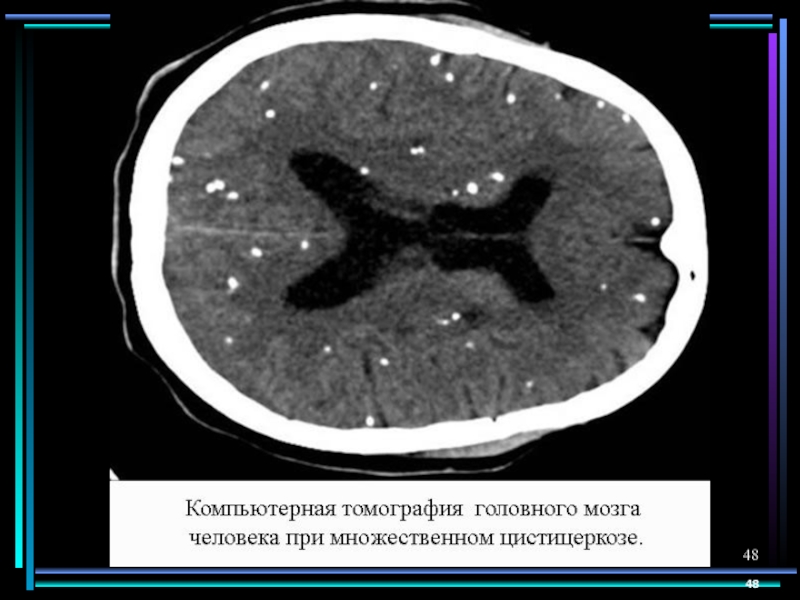

Слайд 47Поражение нервной системы

Трихинеллез

Эхинококкоз

Цистицеркоз

Токсокароз

Стронгило-идоз

Очаговые васкулиты, менингит, под-корковый энцефалит, полинейропатия

Астено-депрессивный синдром, психоз

Симптомы сдавления

вещества голов-ного и спинного мозга, симптомы повышения внутричерепного давления, эпилепсия, энцефалопатия

Гранулемы в головном мозге у детей могут проявляться эпиприступами.

Менингоэнцефалит при выраженном иммунодефиците

Поражение нервной системыТрихинеллезЭхинококкозЦистицеркозТоксокарозСтронгило-идозОчаговые васкулиты, менингит, под-корковый энцефалит, полинейропатияАстено-депрессивный синдром, психозСимптомы сдавления вещества голов-ного и спинного мозга, симптомы